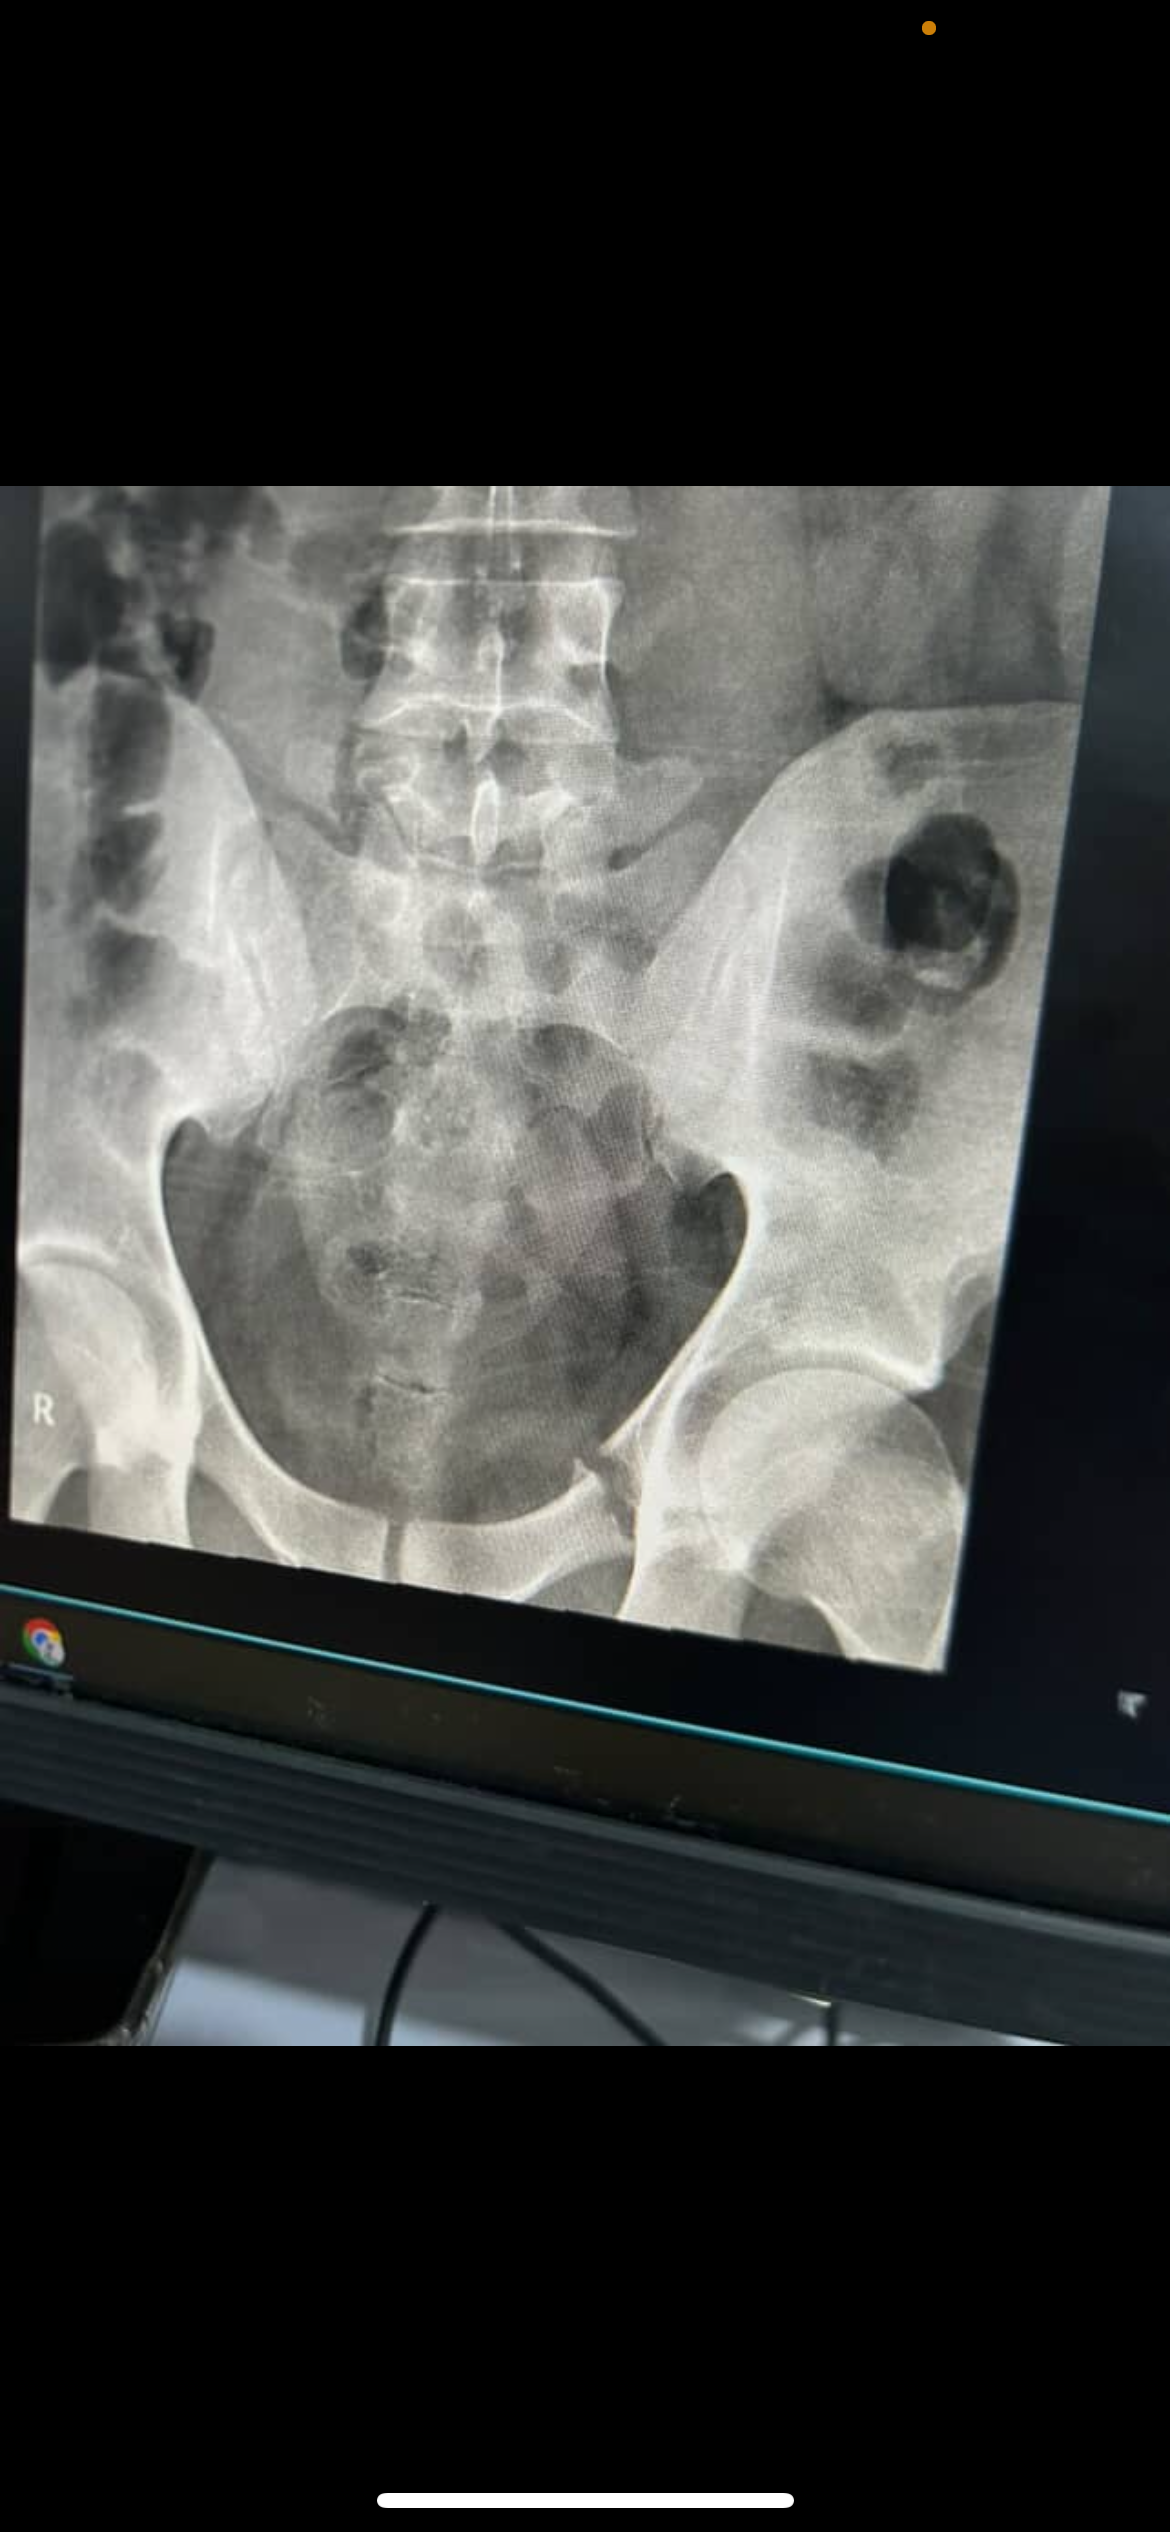

He is currently heavily sedated, with multiple broken bones, including life-threatening internal injuries.